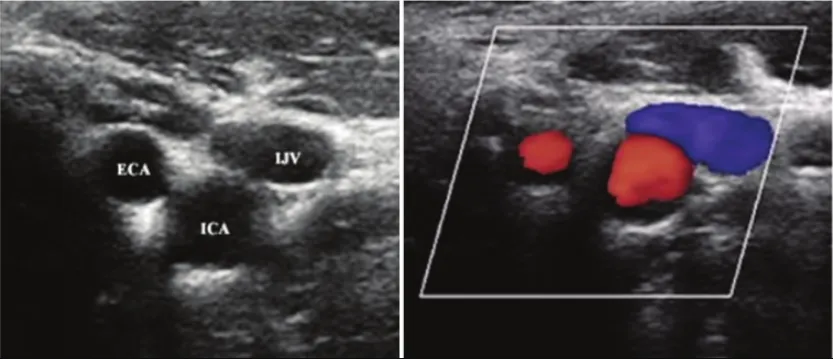

• Siêu âm Doppler: Đánh giá mức độ hẹp tắc và lưu lượng máu trong động mạch.

• Thường được thực hiện qua động mạch đùi dưới hướng dẫn của siêu âm để đảm bảo chính xác và an toàn.